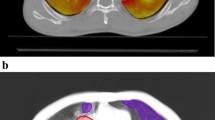

The three-dimensional deformation on the voxel base was recorded, and the Jacobian determinant was calculated based on Eq. 1 by using the MIM toolbar. A Jacobian determinant of 1 represents no volume change during the breathing motion. Voxelized ventilation was defined as a Jacobian determinant minus 1 (Eq. 2) with the assumption that ventilation is indicated by the power of volume changes in the voxels. The ventilation map is shown in Fig. 1a.

In addition, the total lung volume structure was divided into three separate “lung minus GTV” substructures combing lung voxels (the lung was first cropped by 5 mm to eliminate boundary effects) with similar CT densities: > −700 HU is considered a high-density area (H-D), −850 HU to −701 HU is a medium-density area (M-D), and < −850 HU is a low-density area (L-D). Separate 3D islands smaller than 1 cc were excluded from the structures. Contouring of the high-function and high-density lung portions was performed manually in MIM. The definition of the three lung substructures is outlined in Fig. 1b.